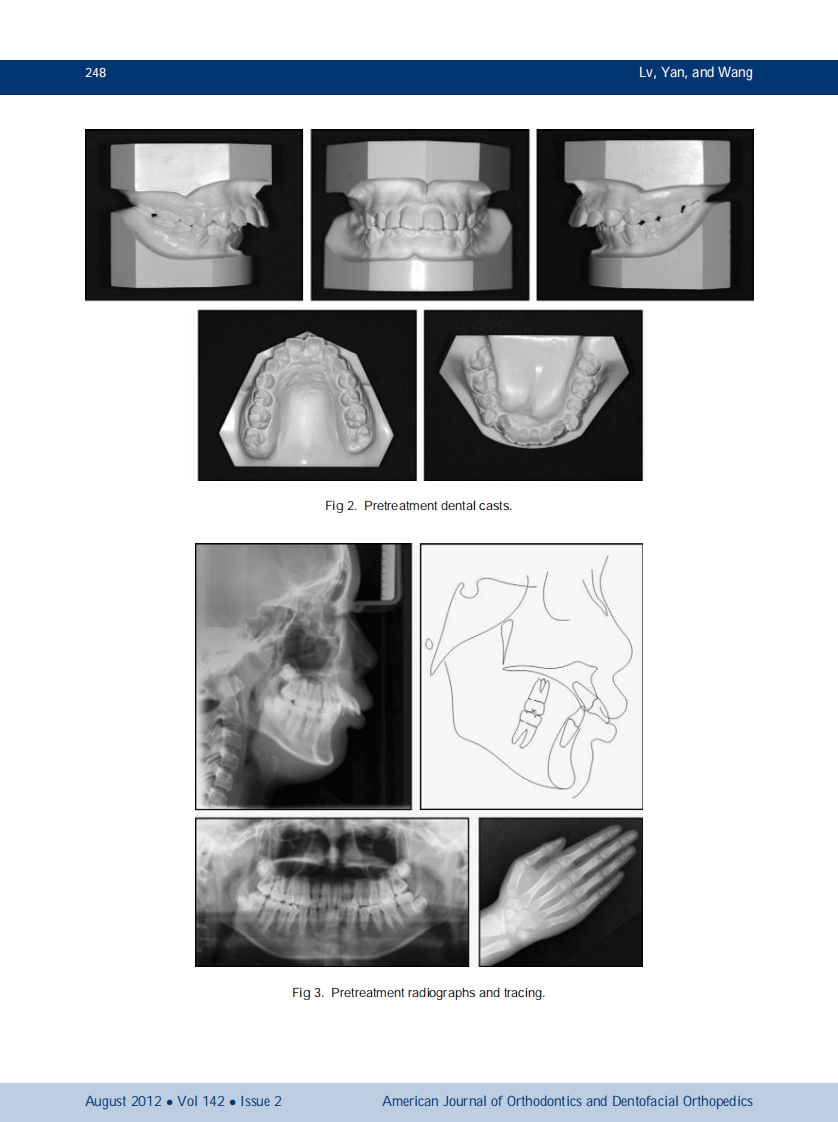

AJO-DO

1-s2.0-S0889540612004490-main.pdf